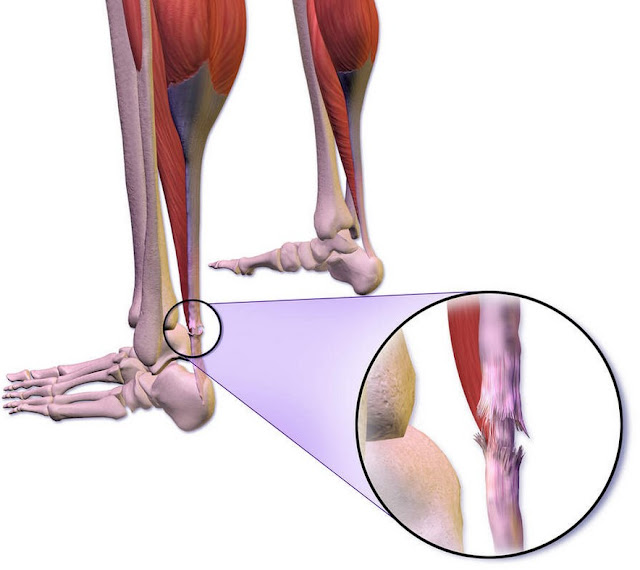

Sudden swelling in one foot or ankle

Most everyday ankle swelling is fairly even in both feet and builds gradually as the day goes on. When swelling appears suddenly in just one foot or ankle, especially within a few hours, it deserves attention. A single swollen foot can signal a blood clot, a torn tendon, an ankle sprain, or even a small fracture you did not realize you had. Sometimes people will notice their shoe on one side no longer fits while the other still does, or they feel a tight band sensation around one ankle.

If you have recently been on a long car or plane ride, had an illness that kept you in bed, or started using a walking boot or cast, call your clinician the same day to ask whether you should be examined or go to urgent care. The key point is the mismatch between your two legs. When one side is clearly more swollen, it is safer to check for a clot or injury sooner rather than later.